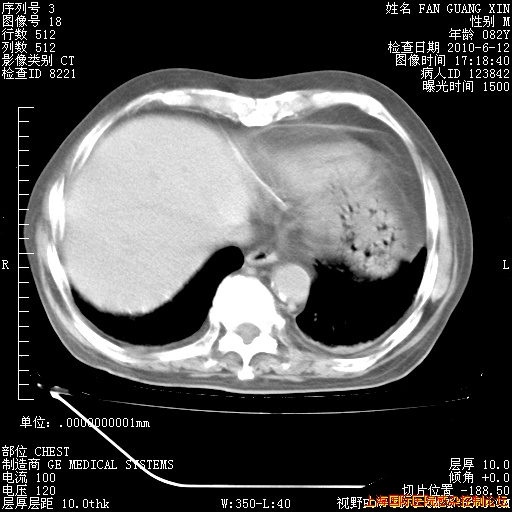

补发6月12日肺部CT肺窗

6月12日肺窗